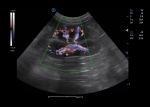

Triplex integrates anatomical imaging, dynamic flow observation and spectral analysis for a comprehensive assessment on vascular disease from multiple perspectives. PW auto correlation being activated during triplex on is to help present another real time quantitative analysis.